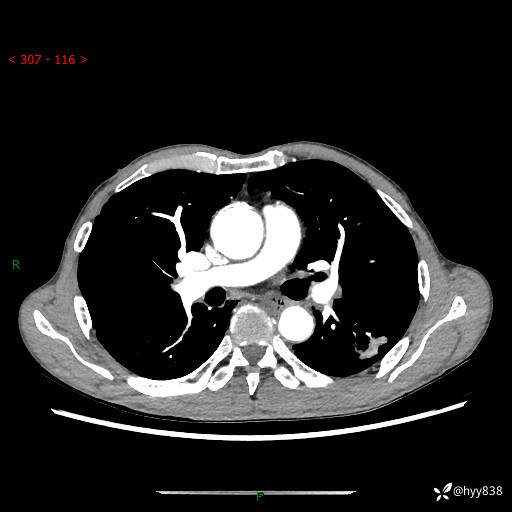

现病史:患者于1月余前无明显诱因出现背部疼痛不适,无明显咳嗽、咳痰、胸闷、咯血、发热等不适,后于2024.5.3至当地市人民医院行胸部CT示:左肺下叶结块,大小约2.2cm*2.6cm,双肺多发小结节,双肺感染性病变,部分纤维增值灶,慢支并双肺局限性肺气肿,肺大泡,纵隔淋巴结增大并部分钙化,冠脉区及大血管壁钙化,双侧胸膜局限性增厚;后口服莫西沙星2周。2024.6.12复查胸部CT示:左肺下叶结块影形态较前饱满,较大截面范围约2.8cm*2.3cm,边缘可见细短毛刺及分叶,性质待查。现患者为求进一步诊治来我院,门诊以“肺占位”收入我科。 起病来,患者精神、食欲、睡眠尚可,大小便正常,体力体重轻微下降。

胸部CT平扫+增强

各期CT值:48hu 100hu 78hu